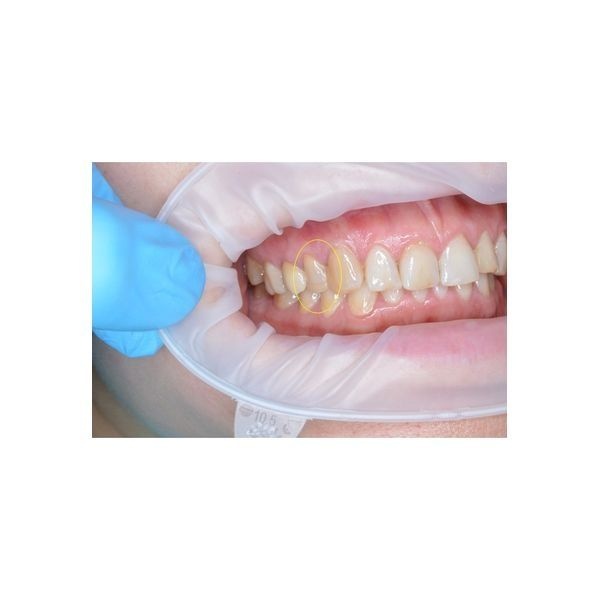

При осмотре полости рта виден зуб верхней правой челюсти, у которого щёчная стенка сохранена, а нёбная — нет. Десна со стороны нёба изменила цвет, при пальпации (прощупывании) и зондировании (проверке с помощью тонкого инструмента — зонда) возникает боль. Глубина дефекта — 5 мм.

По результатам компьютерной томографии:

- выявлен глубокий скол коронковой (видимой) части зуба и корня;

- корневые каналы запломбированы до верхушки;

- признаков воспаления вокруг корня нет.

Пациентку осмотрел врач-ортопед, чтобы понять, можно ли восстановить зуб искусственной коронкой. К сожалению, скол оказался очень глубоким, поэтому сохранить зуб не было возможности. Его рекомендовали удалить.